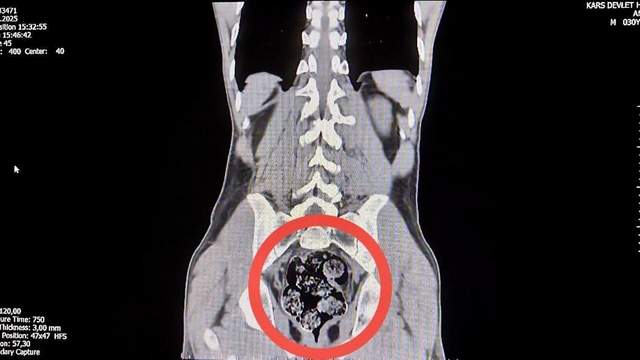

KARS'tahareketlerinden şüphelenilen İran uyruklu yolcunun makatında röntgenle 203 gram metamfetamin tespit edildi. Uyuşturucu, cerrahi operasyonla çıkarıldı.

Kars Emniyet Müdürlüğü Narkotik Suçlarla Mücadele Şube Müdürlüğü ekipleri, Digor-Kars kara yolunda yaptığı uygulamada, Iğdır'dan gelen yolcu otobüsünde arama yaptı. Polis, hareketlerinden şüphelendiği İran uyruklu Jafar Ayrem (42) ve Amır Rafıeı Shekarbaghanı (34) gözaltına aldı. Kars Harakani Devlet Hastanesi'ne götürülen şüphelilerden Shekarbaghanı'nin çekilen röntgeninde, makatında uyuşturucu tespit edildi. 7 parça halinde 203,02 gram metamfetamin, hastanede cerrahi operasyonla çıkarıldı. Emniyetteki işlemlerinin ardından adliyeye sevk edilen şüpheliler, çıkarıldığı hakimlikçe tutuklandı.